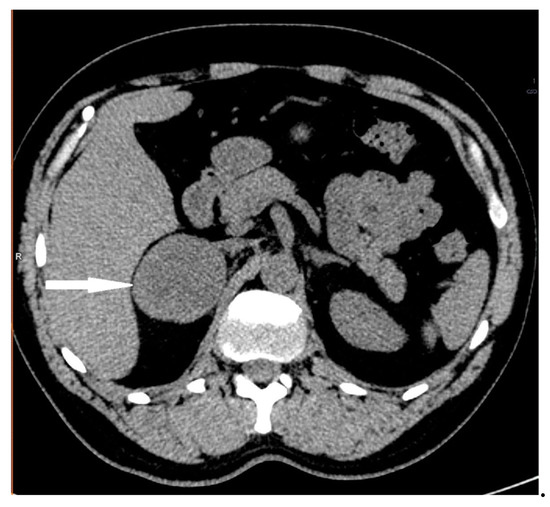

2.2. Case 2

2.3. Case 3

2.4. Case 4

2.5. Case 5

2.6. Case 6

2.7. Case 7